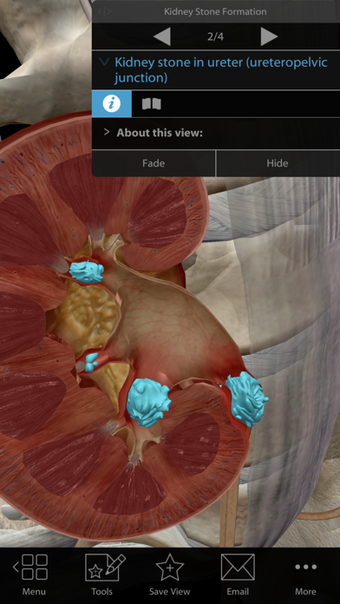

Argosy Publishing による iPhone 用の完全版アプリ。

Physiology Pathologyは iPhone 用のフル バージョンのソフトウェアで、 「医学」カテゴリの一部です。

iPhone用の生理学病理学について

生理学 病理学は、iOS 12.1.2 以降で利用できます。アプリの現在のバージョンは 1.1.39 で、英語、ドイツ語、イタリア語で実行できます。